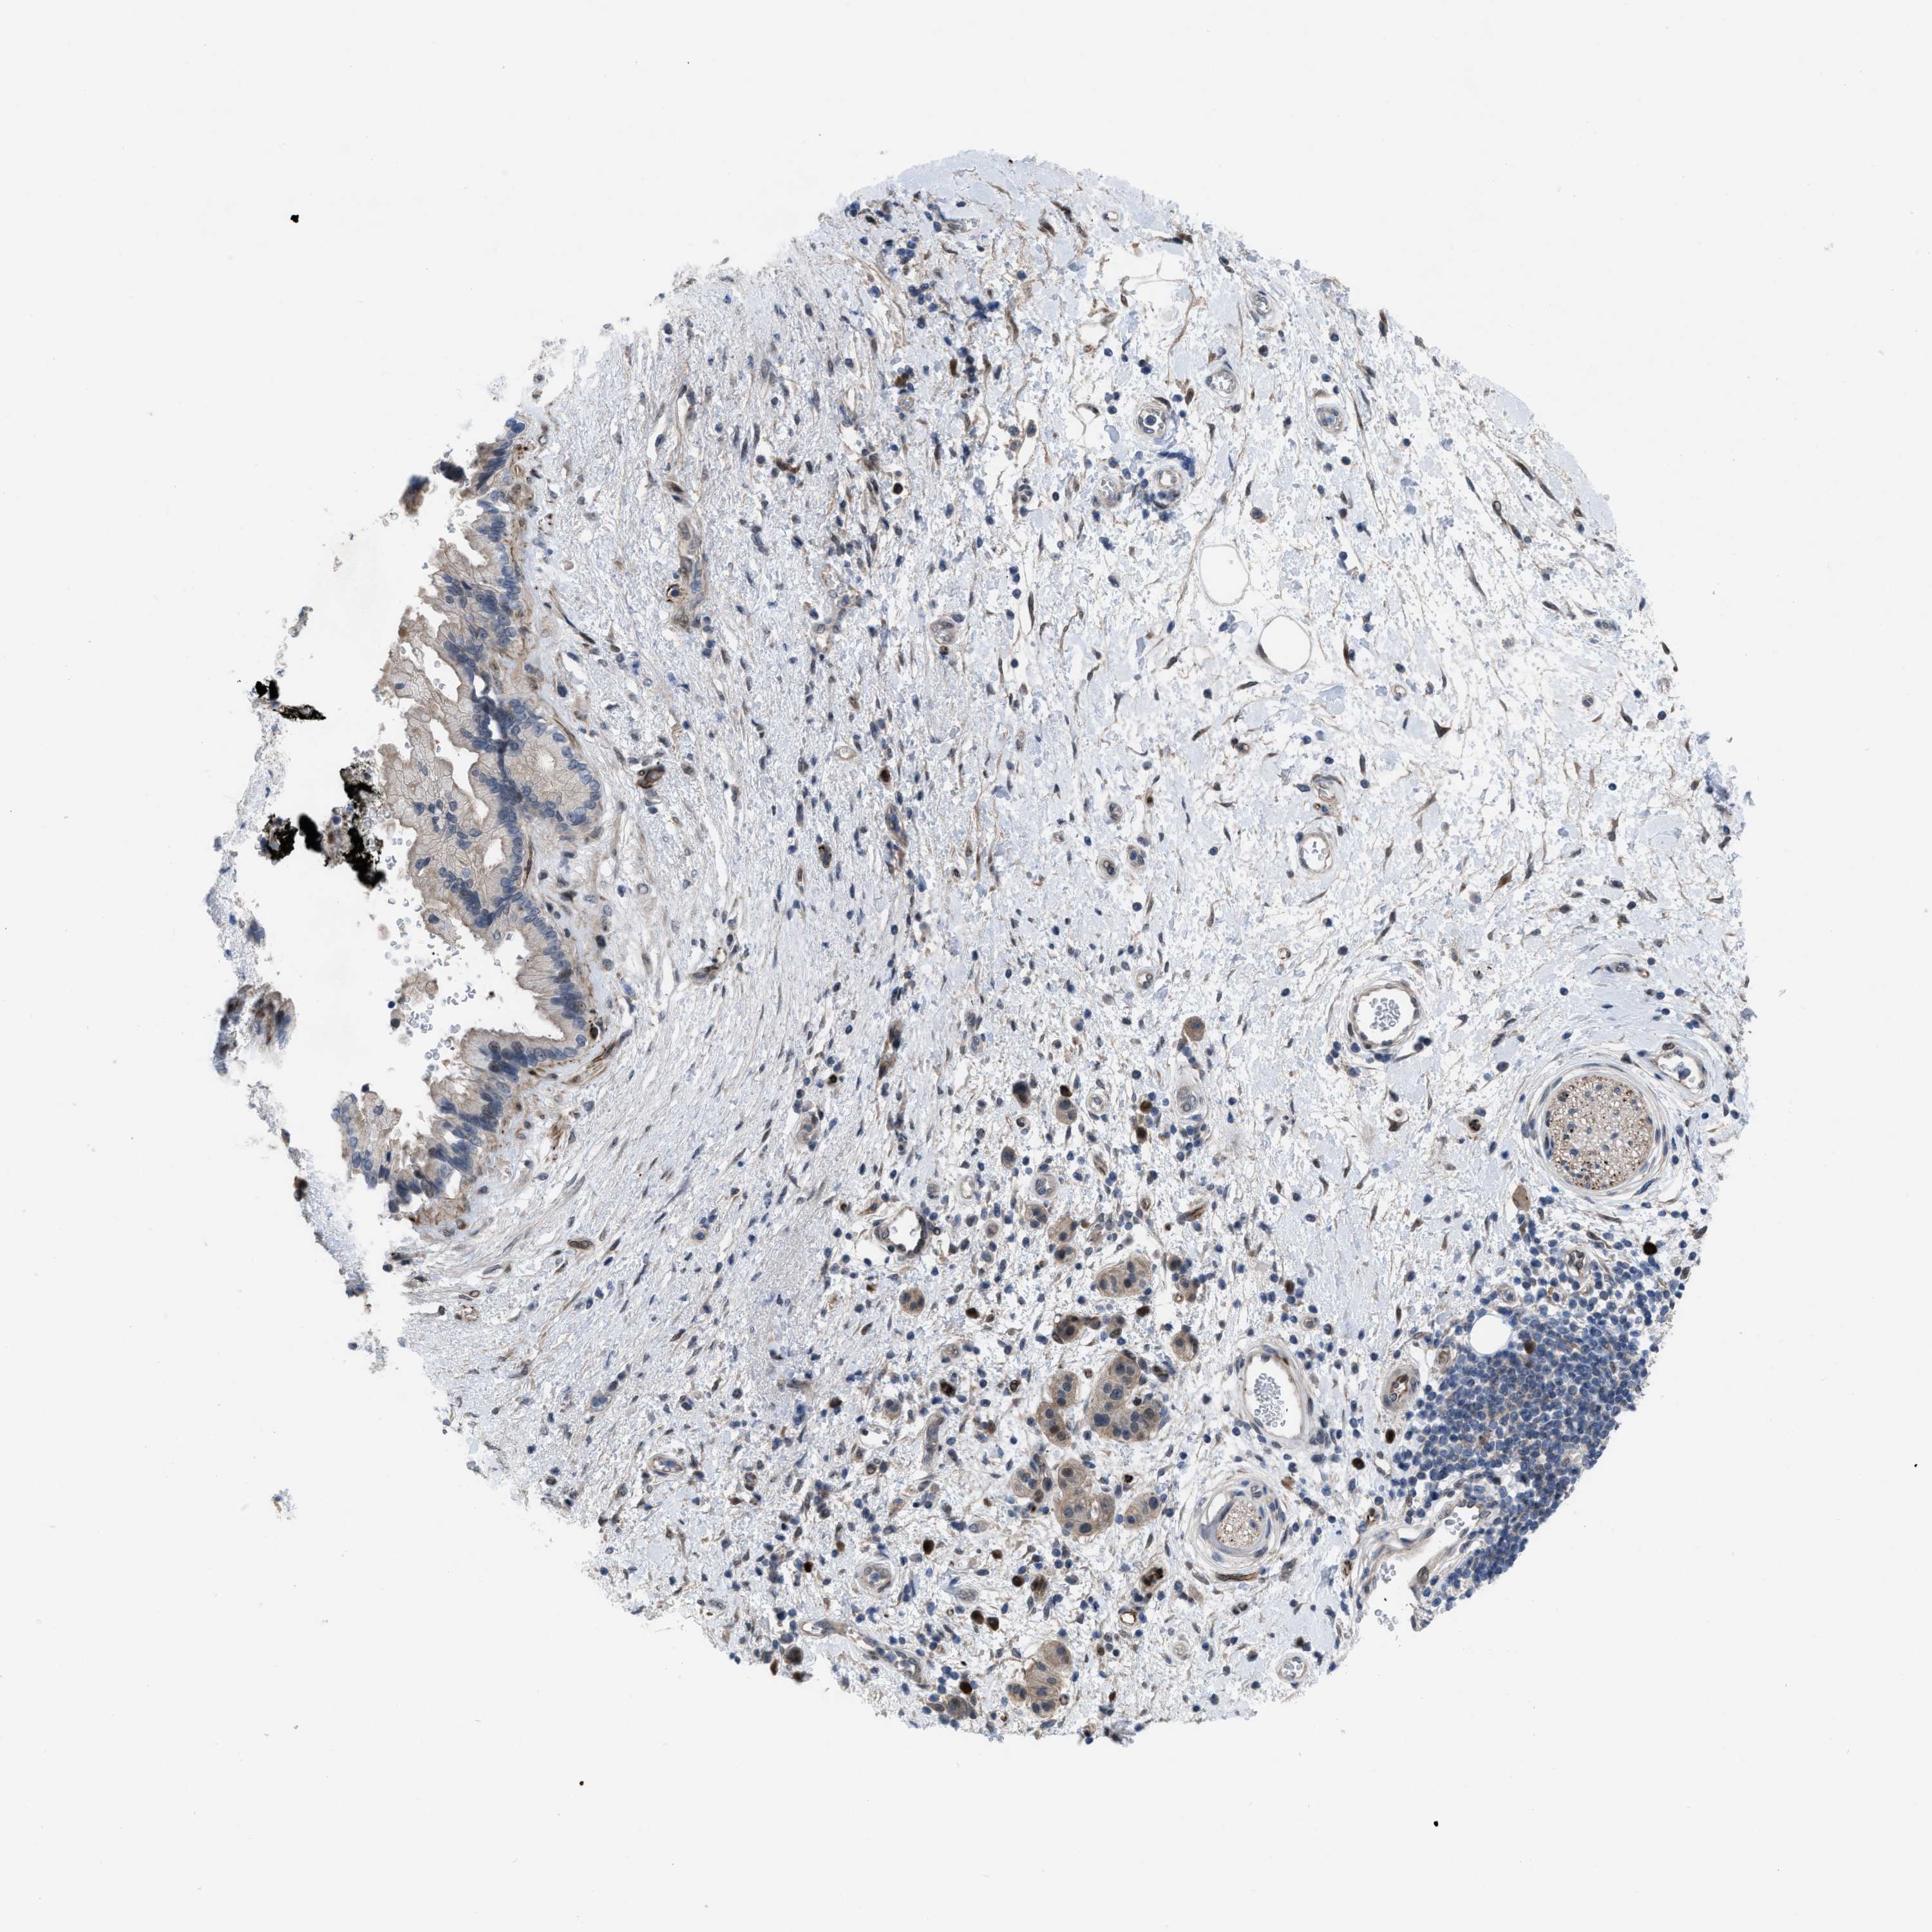

PANCREATIC CANCER - Protein expressioni

A mouse-over function shows sample information and annotation data. Click on an image to view it in a full screen mode. Samples can be filtered based on level of antibody staining by selecting one or several of the following categories: high, medium, low and not detected. The assay and annotation is described here.

Note that samples used for immunohistochemistry by the Human Protein Atlas do not correspond to samples in the TCGA dataset.

Antibody stainingi

Antibody staining in the annotated cell types in the current human tissue is reported as not detected, low, medium, or high, based on conventional immunohistochemistry profiling in selected tissues. This score is based on the combination of the staining intensity and fraction of stained cells.

Each image is clickable and will lead to virtual microscopy that enables deeper exploration of all samples and also displays staining intensity scores, fraction scores and subcellular localization as well as patient and tissue information for each sample.

Antibody HPA019011

Staining

High

Medium

Low

Not detected

Intensity

Strong

Moderate

Weak

Negative

Quantity

>75%

75%-25%

<25%

None

Location

Nuclear

Cytoplasmic/membranous

Cytoplasmic/membranous,nuclear

Adenocarcinoma, NOS